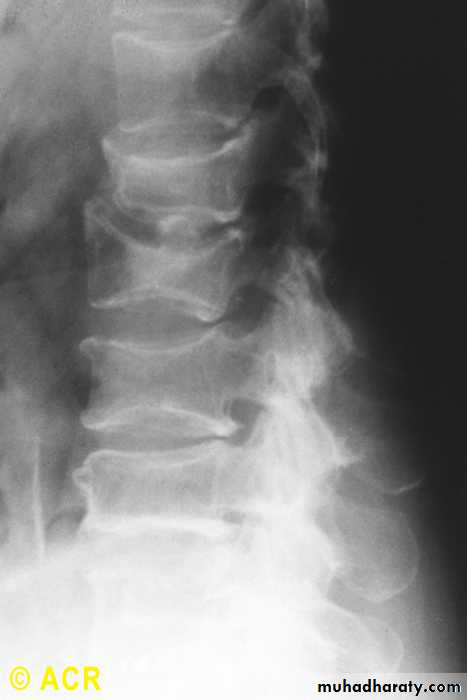

Osteopenia, compression fractures: lumbar vertebrae (radiograph)